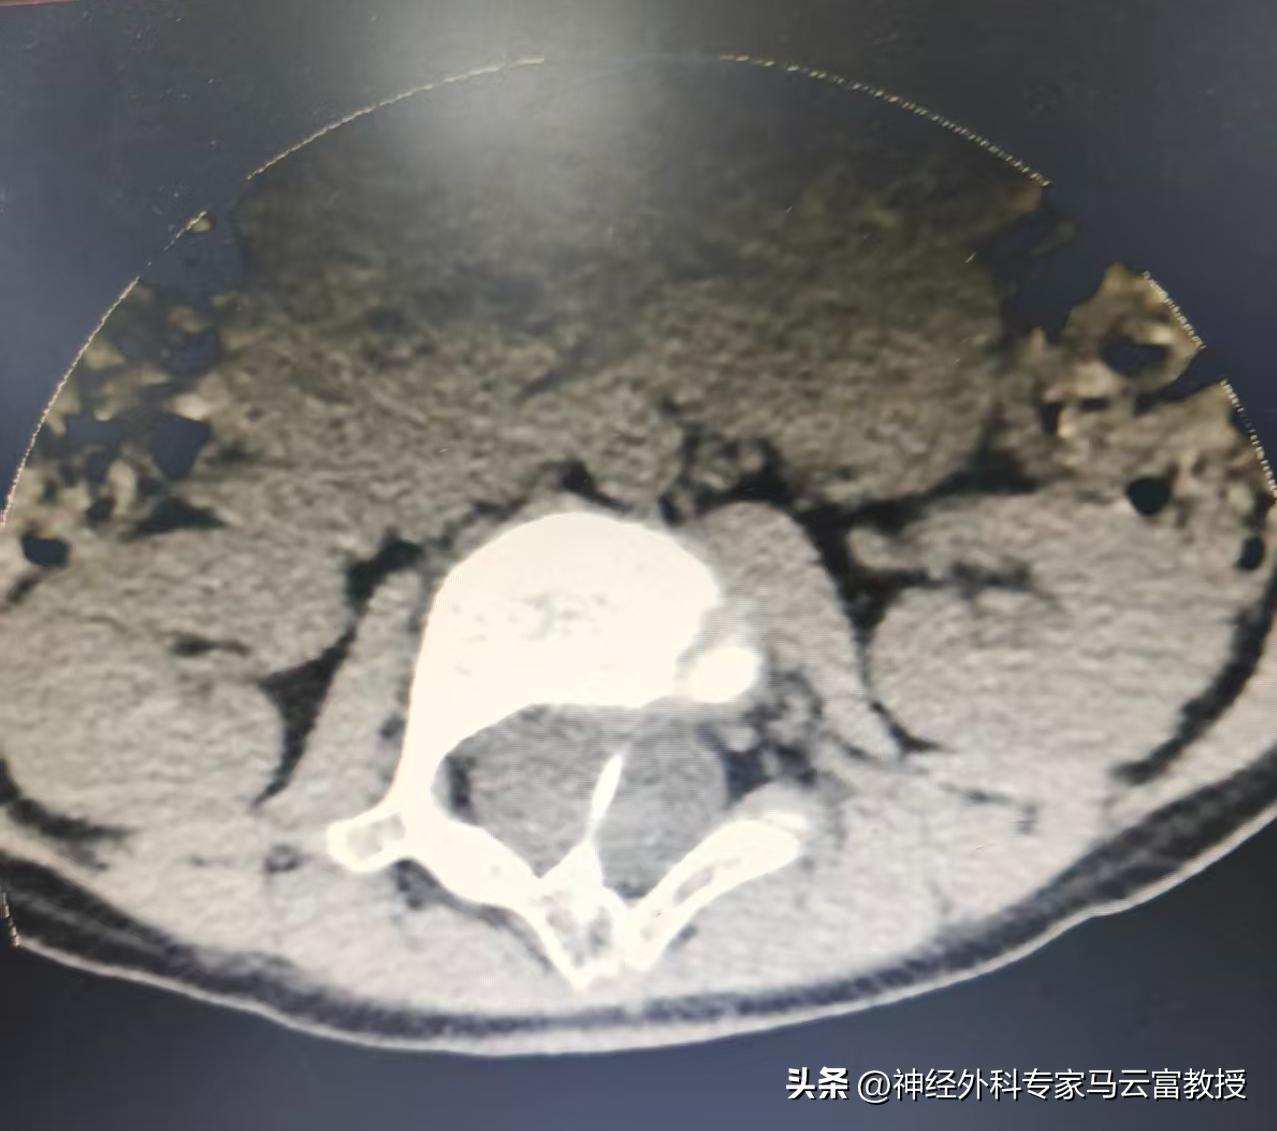

二、什麼是脊髓空洞?

簡單說:脊髓裏面長了 “水泡 / 空腔”,裏面灌滿腦脊液,把原本實心的神經髓質撐空了

三、什麼是脊髓縱裂?

通俗講:本該一根的脊髓,從中間劈成兩半,像一根筷子裂成兩瓣,中間還常夾着骨棘、纖維束、軟骨分隔。